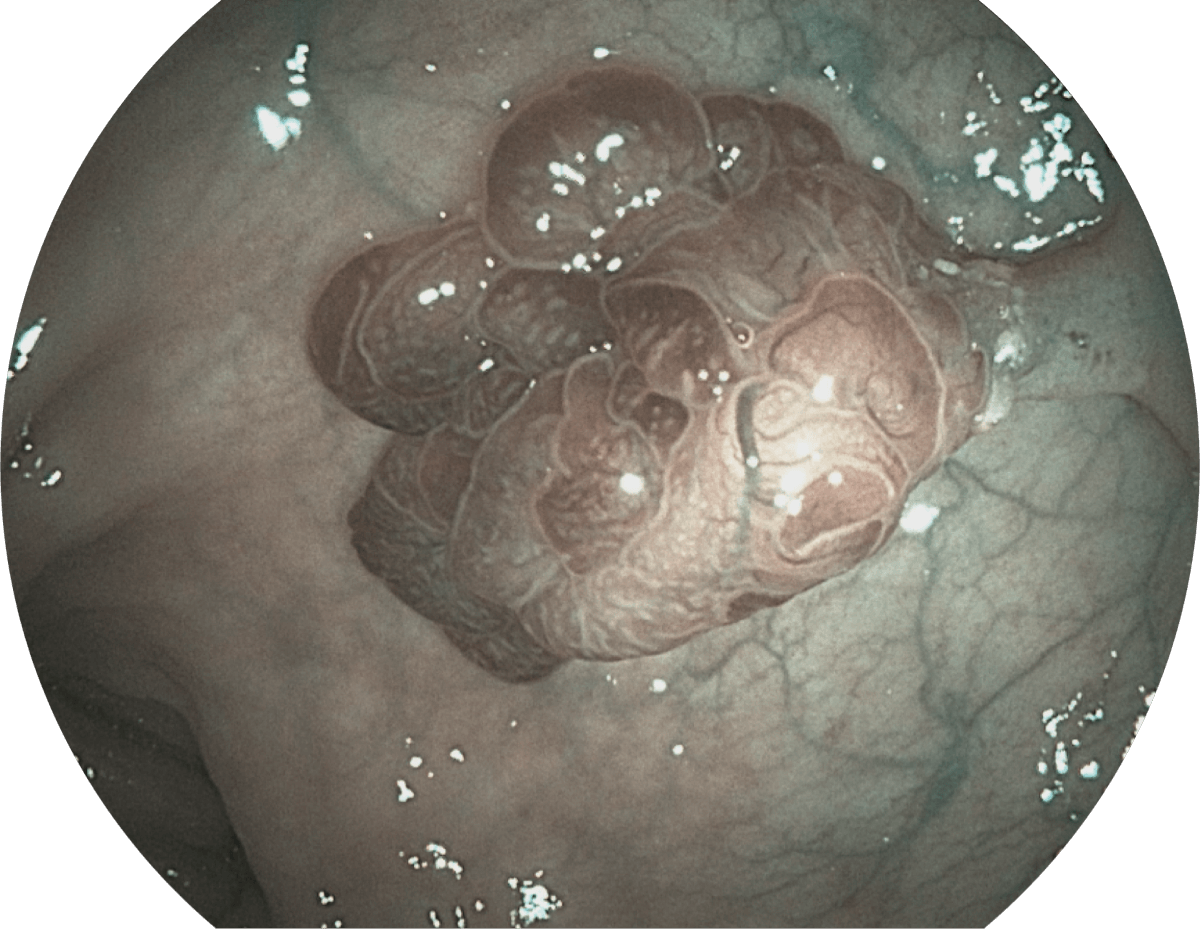

具有聚谱成像技术(SFI)及光电复合染色成像技术(VIST),可完美呈现粘膜细节及病变特征。

(Spectral Focused lmaging, SFI)

( Versatile Intelligent Staining Technology, VIST )

WL

SFI

VIST